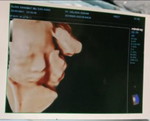

ibu of 1 tampan pesulap

Bạcibu of 1 tampan pesulap